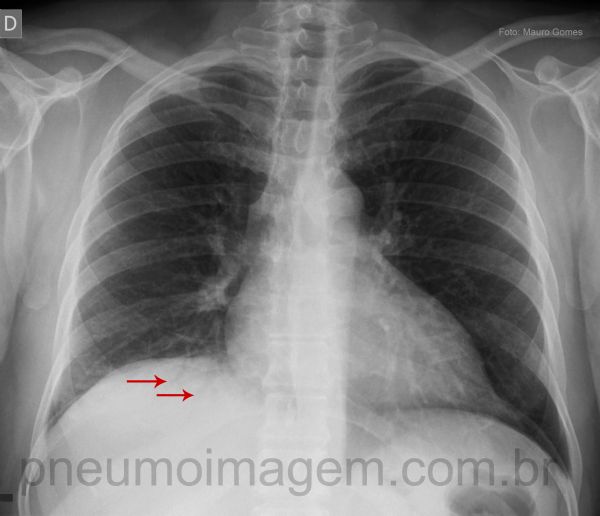

Voltando agora à radiografia em PA, percebe-se que há uma assimetria entre as cúpulas frênicas, com a direita mais elevada que a esquerda. Isso provavelmente é determinado pela atelectasia segmentar presente no lobo inferior direito. Também é possível notar que atrás da linha do diafragma existe uma opacidade com a presença de broncogramas aéreos no seu interior (setas vermelhas), demonstrando a região com pneumonia.

Asymmetry between the hemidiaphragm with the right higher than the left. This probably is determined by segmental atelectasis present in the right lower lobe. Looking closely you can see that behind the line of the diaphragm is an opacity with the presence of air bronchograms inside (red arrows), demonstrating the region with pneumonia.